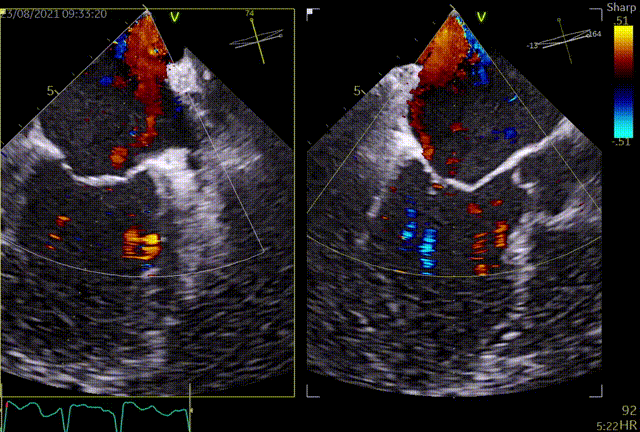

手术于全麻下进行,手术采用经典股静脉房间隔途径,房间隔穿刺后置入24F导引导管及二尖瓣夹输送系统,在TEE引导下准确植入一枚二尖瓣夹,瓣膜夹位置稳定,植入后返流基本消失,二尖瓣跨瓣平均压力阶差4mmHg,双孔化形成,遂移除器械输送系统。患者术后恢复良好,瓣膜夹位置稳定,拟于近期出院。此次手术得到了医院领导、心胸外科、麻醉科、体外循环组、重症医学科及医务科等科室的大力支持。

术后TEE提示,二尖瓣夹植入后返流基本消失,双孔化形成